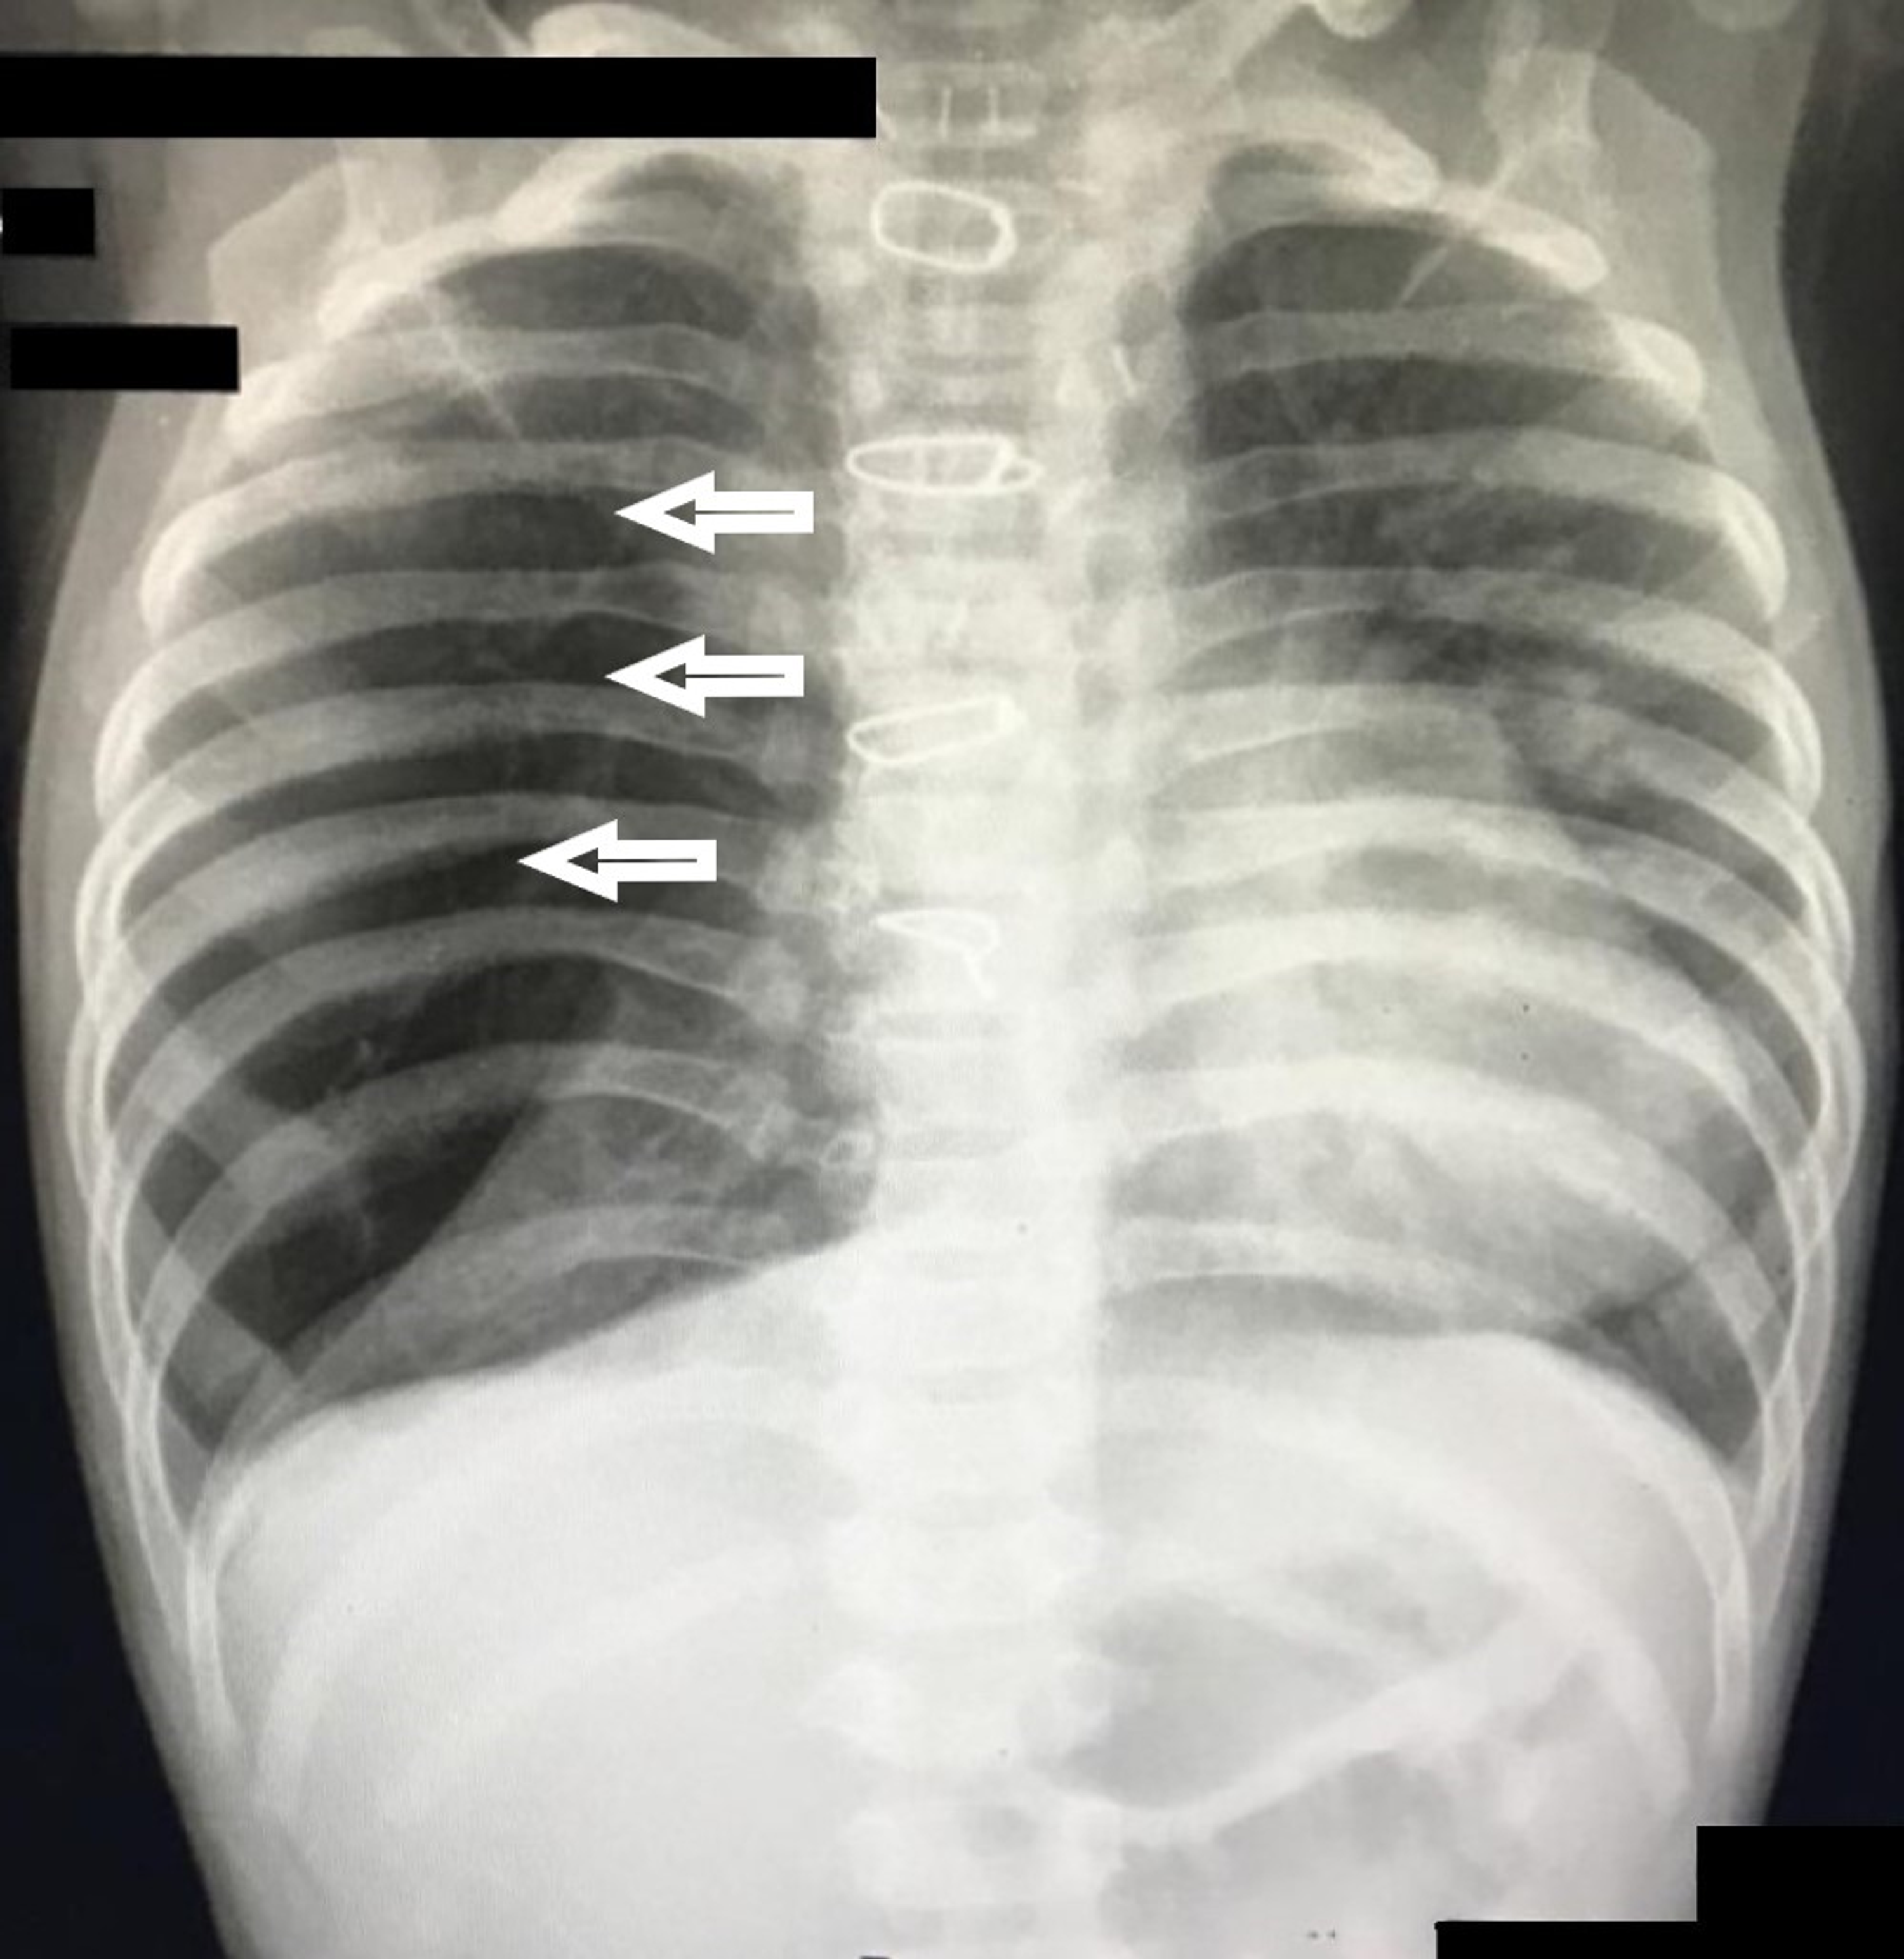

Radiolucent expanded right lung in a newborn, compatible with congenital lobar emphysema (rml & rul). congenital lobar emphysema (cle), also known as congenital alveolar overdistension, is a developmental. congenital lobar emphysema is a rare lung malformation, with an estimated incidence of one case per 20. the hrct findings were characteristic of congenital lobar emphysema (cle). congenital lobar emphysema (cle).

Congenital lobar emphysema (CLE). Chest radiograph of a 4monthold boy Congenital Lobar Emphysema Chest X Ray congenital lobar emphysema is a rare lung malformation, with an estimated incidence of one case per 20. the hrct findings were characteristic of congenital lobar emphysema (cle). Radiolucent expanded right lung in a newborn, compatible with congenital lobar emphysema (rml & rul). congenital lobar emphysema (cle). congenital lobar emphysema (cle), also known as congenital alveolar overdistension,. Congenital Lobar Emphysema Chest X Ray.